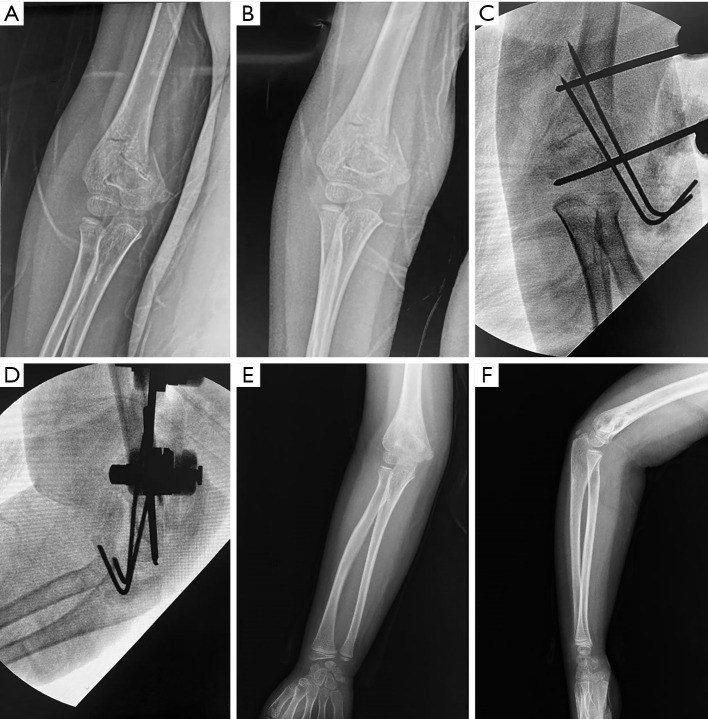

Background: Medial comminuted supracondylar humeral fracture (SCHF) is a common elbow injury in children, and there is no consensus on treatment yet. While crossed pinning offers biomechanical advantages for medial comminution, it carries inherent risks of iatrogenic ulnar nerve injury. This study aims to describe the surgical technique of lateral external fixation (LEF) combined with K-wire (KW) as an alternative technique and evaluate the clinical and radiological outcomes of this method.

Methods: We retrospectively analyzed 53 children (mean age 7.1 years; 28 males, 25 females) with Gartland type II (n=9) and III (n=44) SCHFs with medial comminution, treated between January 2019 and January 2022. All fractures were fixed with LEF and KW. Functional outcomes were assessed using Flynn's criteria, with radiological parameters (carrying-angle loss, shaft condylar angle, Baumann's angle) measured at a minimum 12-month follow-up (range, 12-26 months).

Results: At last follow-up, radiographic evaluation demonstrated a mean shaft condylar angle of 37.1°±4.4°, Baumann's angle of 75.6°±3.6°, and carrying angle loss of 3.4°±2.0°. Range-of-motion loss averaged 3.5°±2.4°. According to Flynn's criteria, 87% (46/53) achieved excellent and 13% (7/53) good outcomes. Subgroup analysis revealed significantly greater carrying-angle deviation (P<0.01) and motion loss (P=0.05) in Gartland III versus II fractures. Complications included two superficial pin-site infections (3.8%) resolved with oral antibiotics; no instances of iatrogenic nerve injury, vascular compromise, or malunion occurred.

Conclusions: For pediatric SCHF with medial comminution, external fixator (EF) plus KW is a feasible alternative without the risk of iatrogenic ulnar nerve injury.